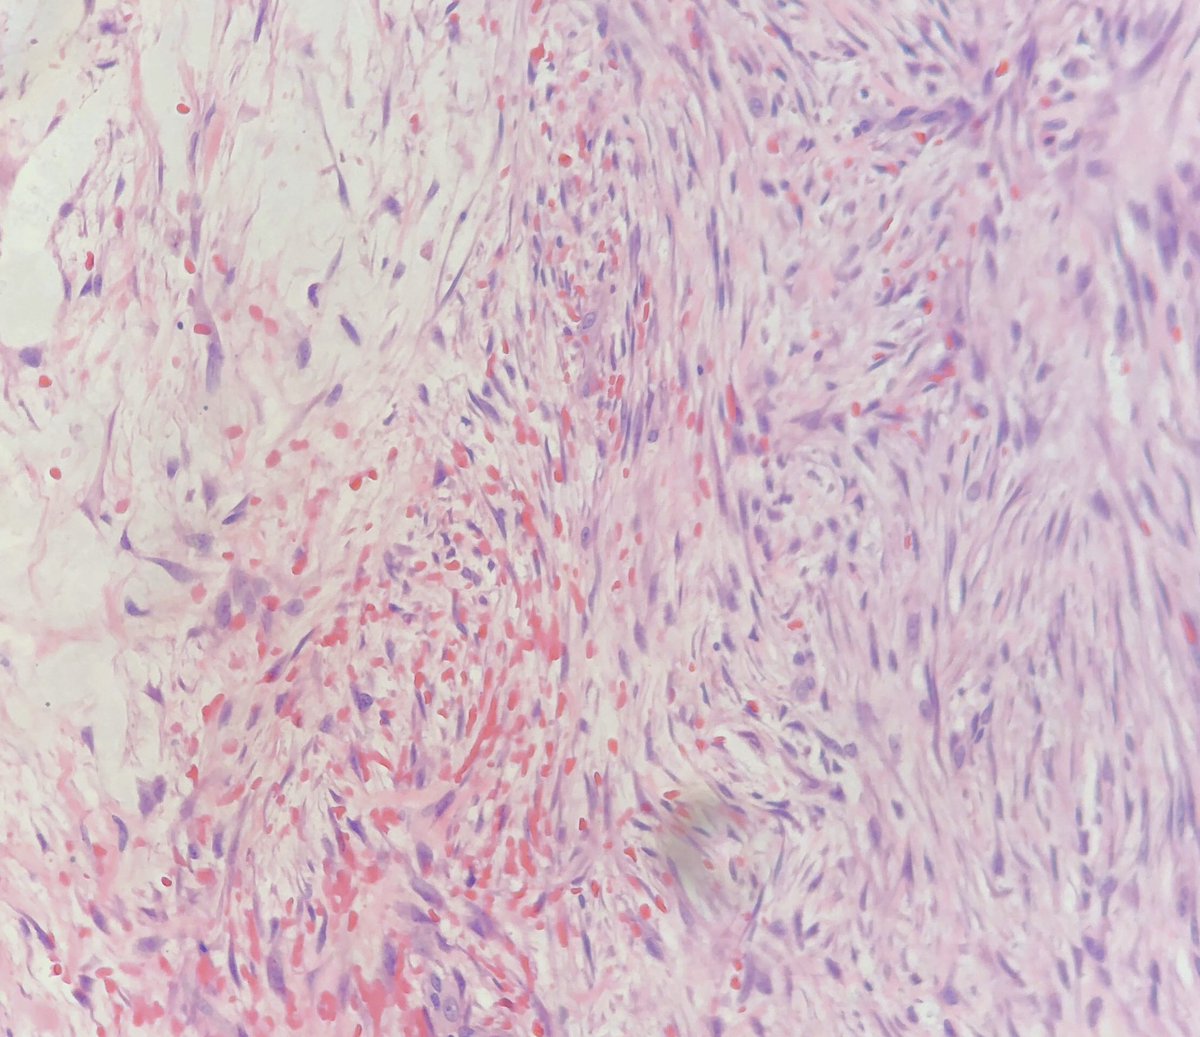

A beautiful

45 year old man with a postauricular mass

spindled and stellate plump cells in fascicular arrangement with myxoid stroma and extravasated RBCs

SMA+, Keratin-, S100-, cytoplasmic b-Catenin

USP6 gene rearranged